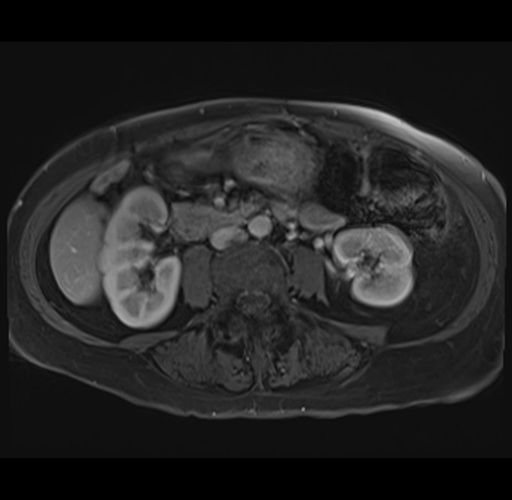

MRI T1

Imaging analysis